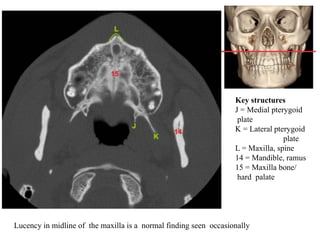

Key structures

H = Maxillary sinus,

anterior wall

I = Maxillary sinus,

medial wall

J = Medial pterygoid

plate

K = Lateral pterygoid

9 = Maxillary sinus

14 = Mandible, ramus

Fracture of the pterygoid plates may represent LeFort fracture

L = Maxilla, spine

15 = Maxilla bone/

hard palate

Lucency in midline of the maxilla is a normal finding seen occasionally